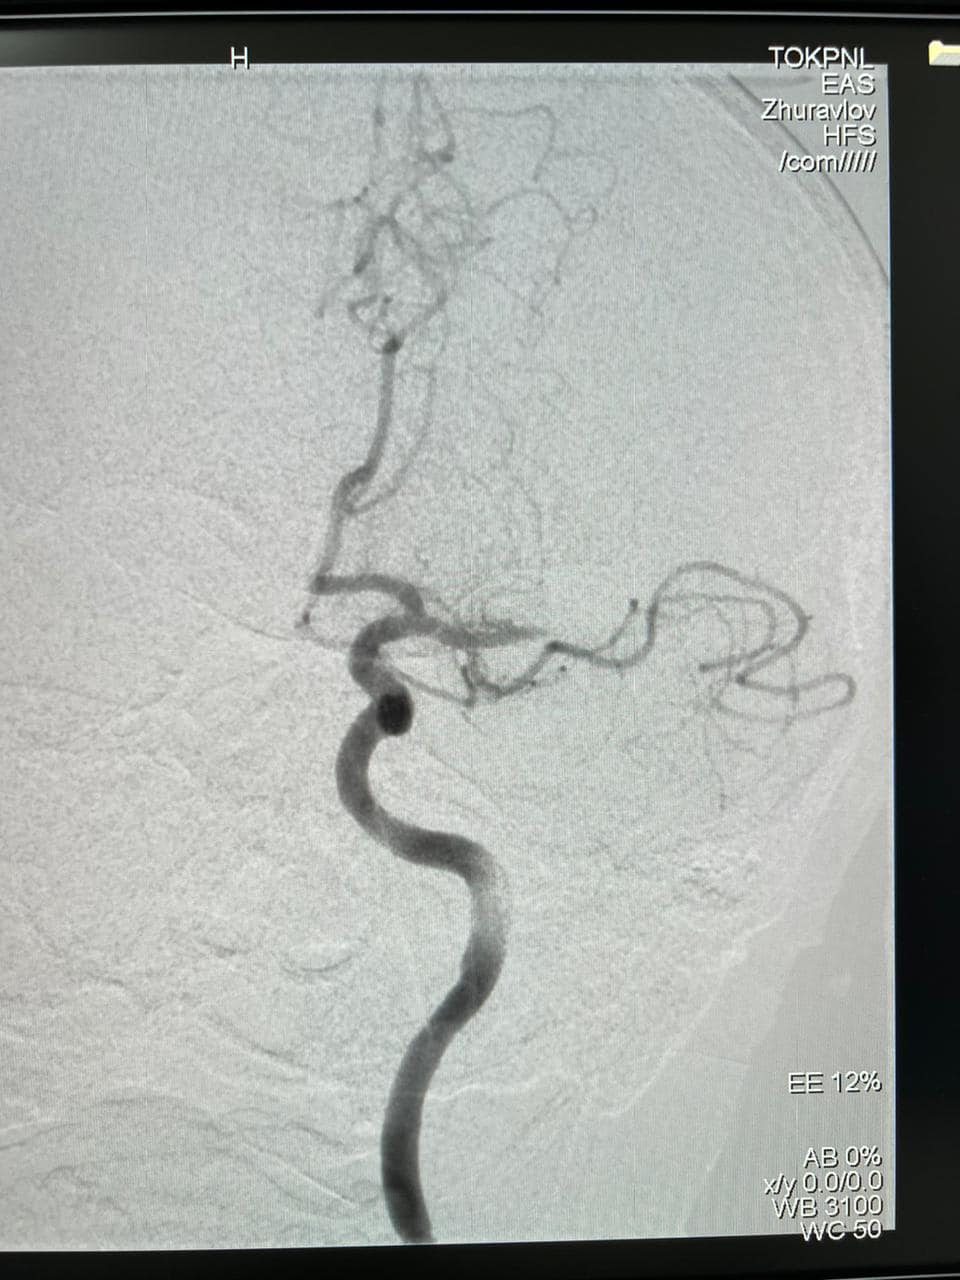

Вперше у Тернопільській області медики нейрохірургічного відділення Тернопільської обласної психоневрологічної лікарні виконали операцію — тромбектомію з дрібних гілок лівої середньої мозкової артерії.

Пацієнт був доставлений до реанімаційного відділення ургентно. При поступленні у нього була відсутня мова та не рухалися праві кінцівки. При КТ-ангіографії був виявлений тромбоз лобної гілки лівої середньої мозкової артерії.

Спочатку лікарі зробили тромболізис, після якої у хворого відновилися рухи у правій руці та частково мова. Лікарі прийняли рішення виконати тромбектомію.

В результаті операції у хворого вдалося відкрити велику гілку лівої середньої мозкової артерії та відновити кровообіг по більшості судин басейну.

Операцію провели лікарі-інтервенціоналіст Гаджальський В.В., асистент Журавльов О.Ф., анестезіолог Мусієнко А.М., під керівництвом завідувача нейрохірургічним відділенням, лікаря з 20-ти річним стажем роботи у Херсоні — Олексія Леонтьєва.